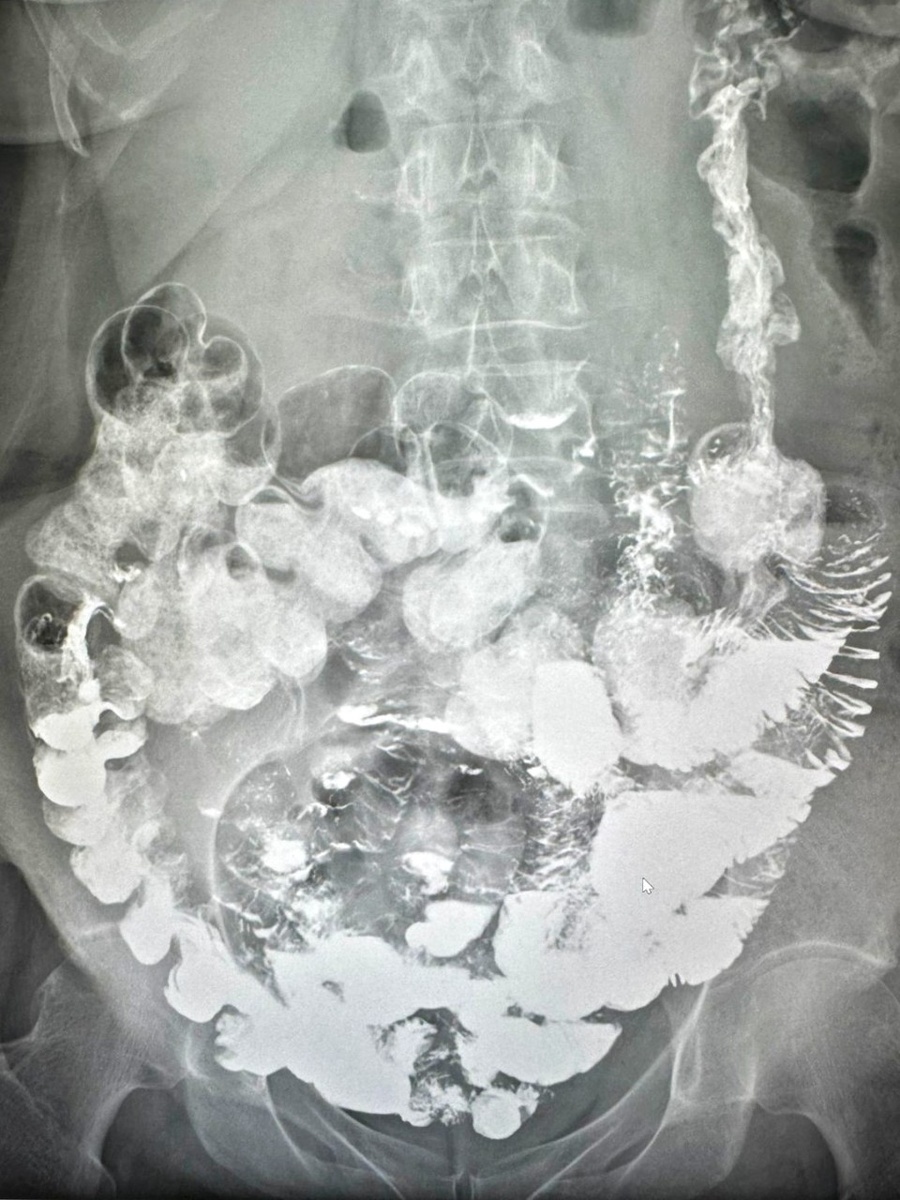

При первичном осмотре гастроэнтеролог А.А.Атаева тщательно собрала анамнез и изучила предоставленную медицинскую документацию. Для уточнения диагноза и определения дальнейшей тактики лечения врач рекомендовала дополнительное обследование, которое ранее пациентке не проводили - рентгенологическое исследование с пассажем бария.

По результатам рентгенологическое исследование пассажа бария по ЖКТ выявлены признаки синдрома Пайра (высокая фиксация селезеночного изгиба) и трансверзоптоз. На основании жалоб, анамнеза и полученных данных при обследовании был установлен диагноз: болезнь Пайра.